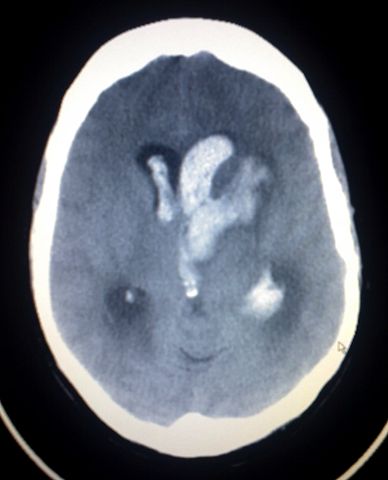

This image shows an Intracerebral and Intraventriclar haemorrhage of a young woman. The woman was one week post partum, with no known trauma involved.

| current | 16:32, 24 June 2007 | 1,200×1,484 (205 KB) | Glitzy queen00 ( Talk | contribs) | (This image shows an Intracerebral haemorrage of a young woman. This bleed was spontaneous with no known trauma involved.) |